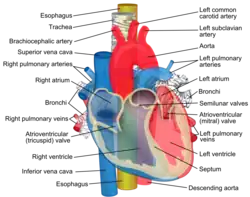

| Esophagus | |

The digestive tract, with the esophagus marked in red | |

| Details | |

| Precursor | Foregut |

| System | Digestive system |

| Artery | Esophageal arteries |

| Vein | Esophageal veins |

| Nerve | Sympathetic trunk, vagus |